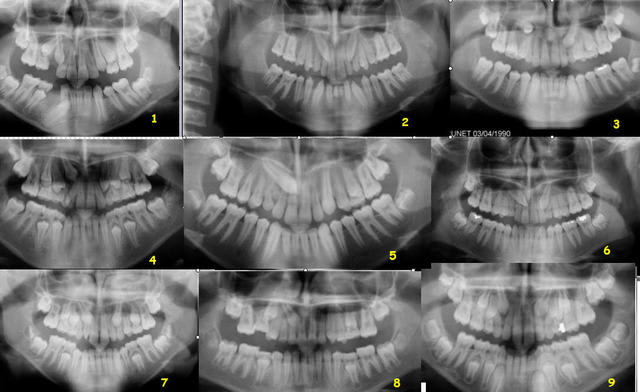

J'ai oublié de remettre le montage initial.

Voici.

Daniel

Test canines js2p4u - Eugenol